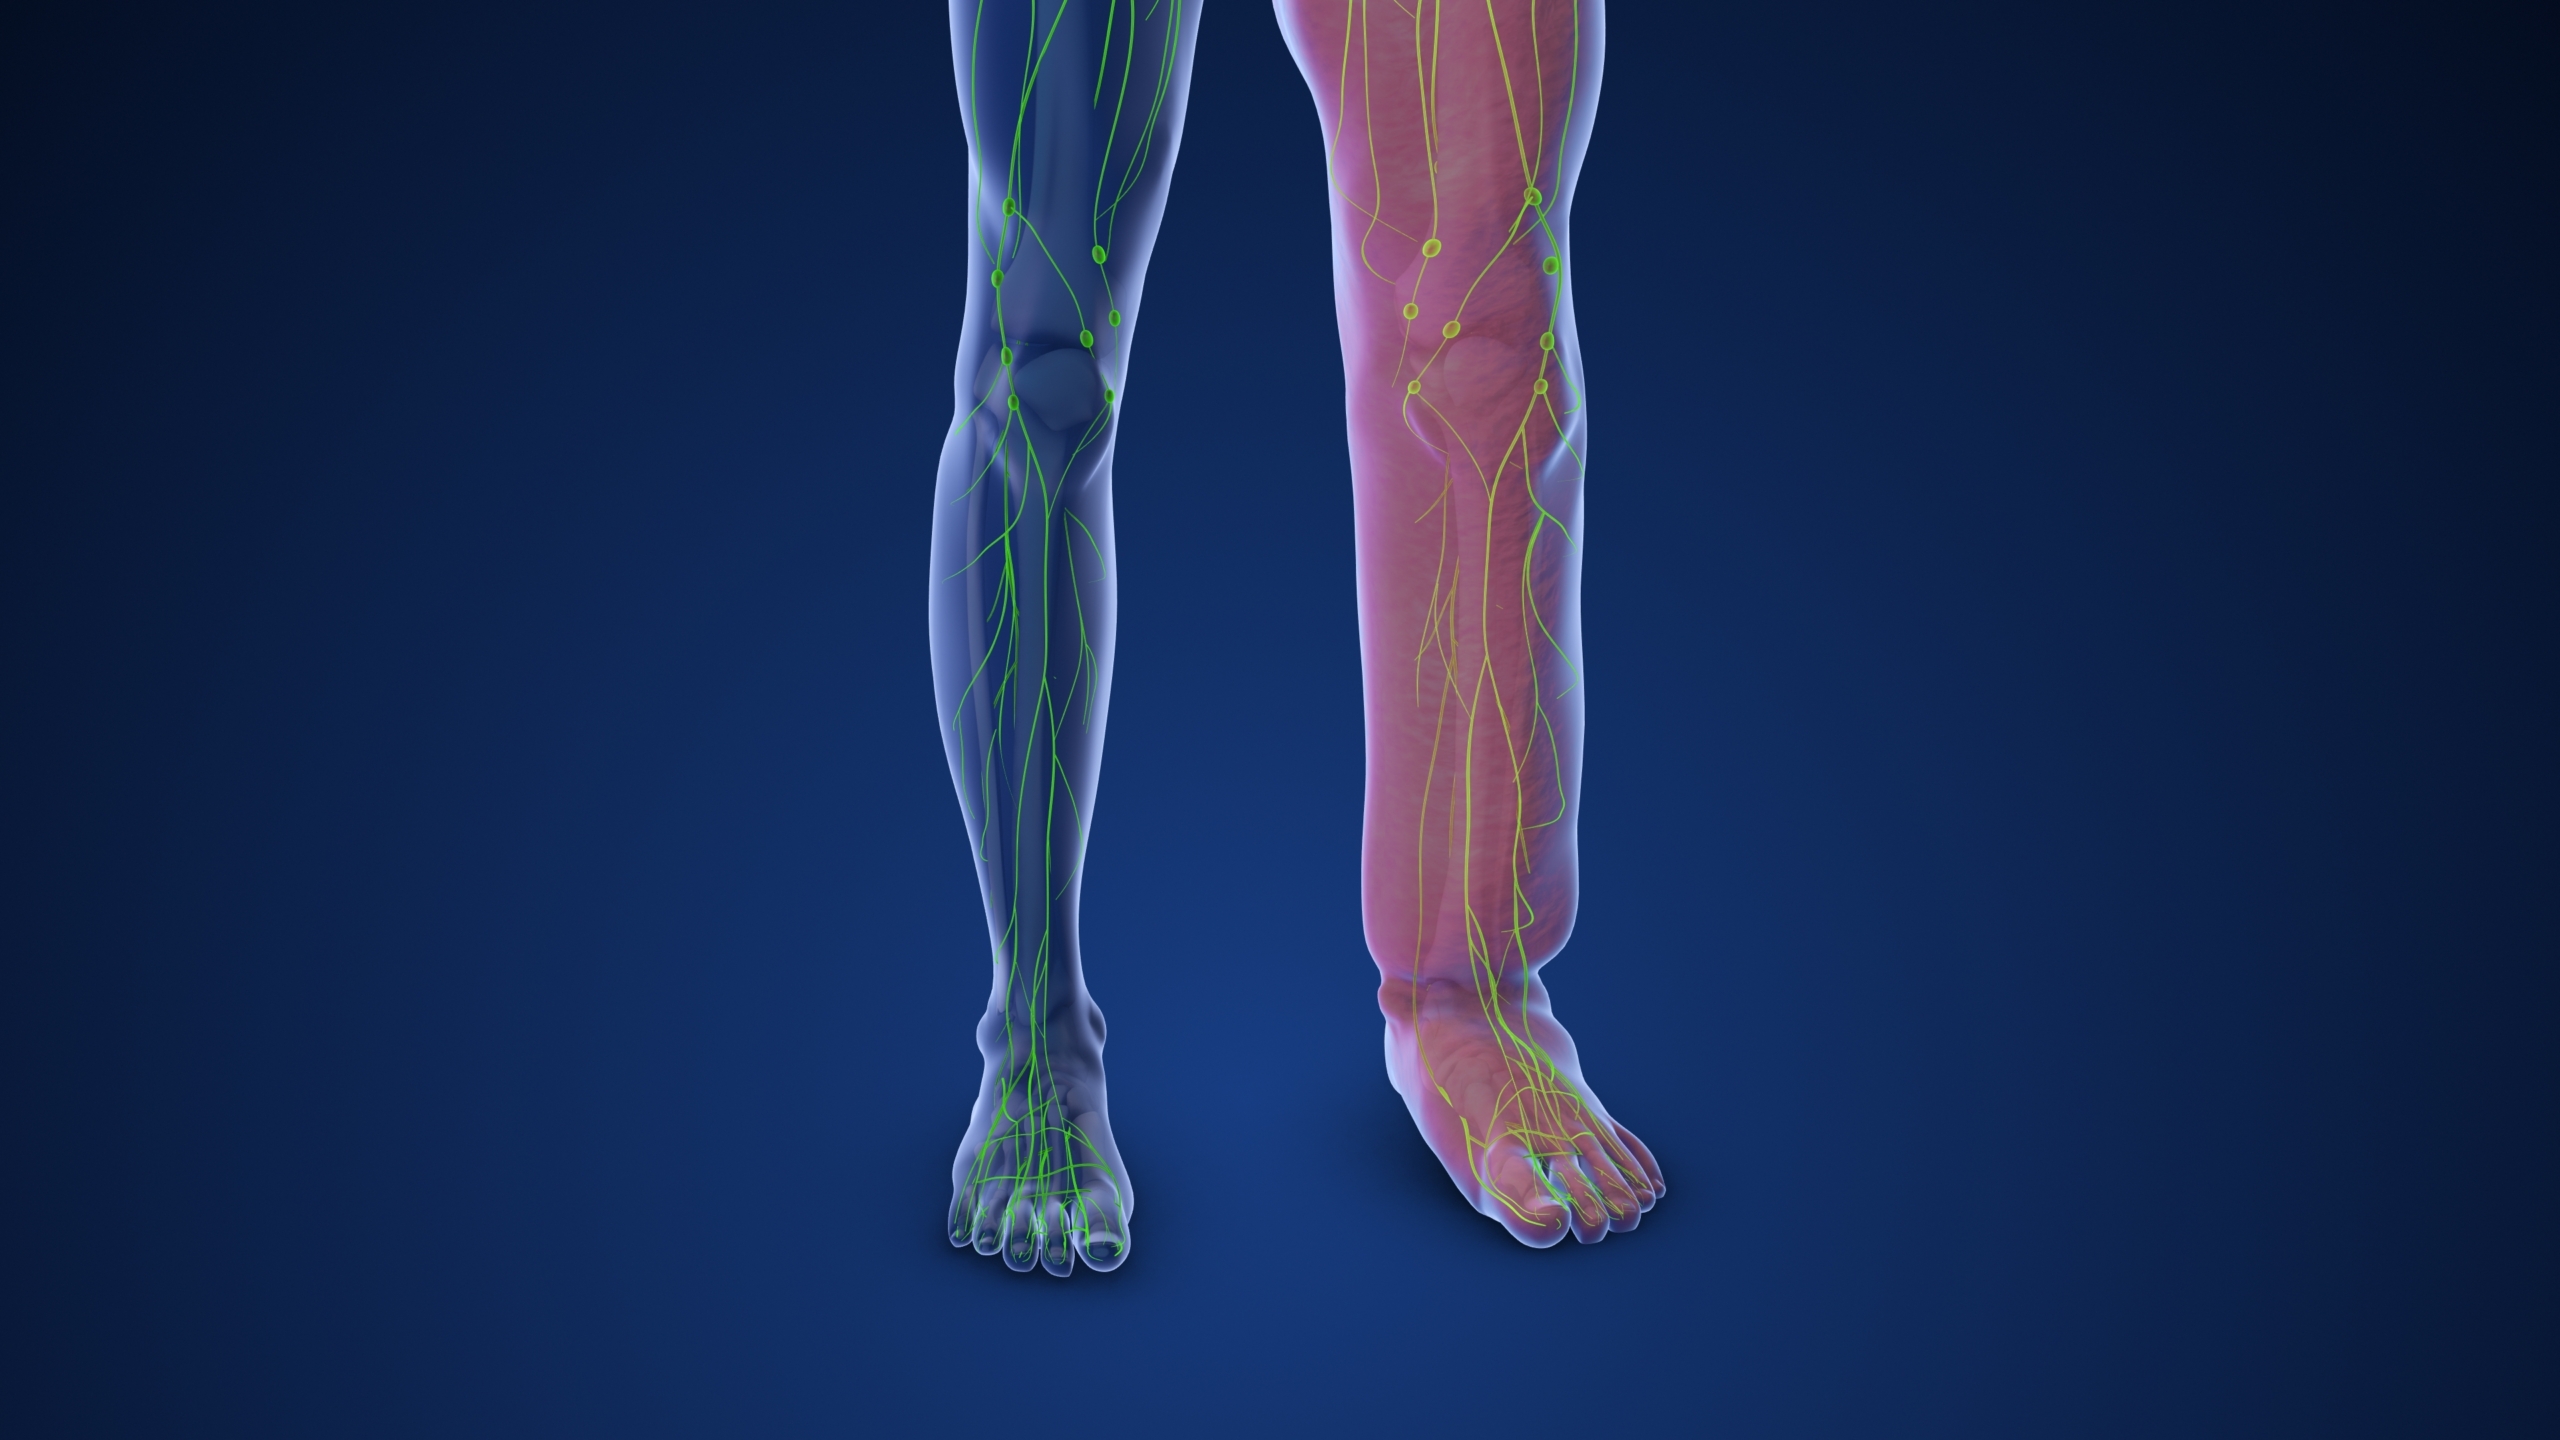

You may know that the immune system defends the body against disease. But did you know that it has a special circulatory structure called the lymphatic system that helps it do its job? When that special system gets impaired, a condition called lymphedema can occur, causing uncomfortable swelling in the arm or leg, which needs to be treated by a health care provider before an infection occurs.

The lymphatic system defends against disease, maintains blood pressure and transports hormones, nutrients and waste products. To perform these functions, it involves tonsils, spleen, thymus, lymph nodes, lymph vessels and white blood cells. When the lymphatic system is working properly, its system of lymph vessels circulates lymph (i.e., a fluid containing protein, water, cells, waste products and fat) through blood and tissues, while absorbing protein, fat and vitamins, and recognizing/removing waste products (e.g., germs, foreign substances and cancer cells). Hanf said the lymphatic system is a lot like a sewage treatment plant.

Lymphedema develops when the lymphatic system becomes damaged from chronic infections, scar tissue or cancer/cancer therapy, and causes an abnormal accumulation of protein-rich lymph in the tissues just beneath the skin that results in swelling. Hanf likens it to a bucket with a clogged spigot that cannot release the water it’s collecting. Although this accumulation typically occurs in the arm or leg, it can also occur in the breast, chest, head, neck, abdomen and genitals.

Along with swelling in their arm or leg, patients with lymphedema often report feeling heaviness or tingling sensations in a limb. Other symptoms include tingling starting in the fingers and toes, decreased range of motion, limb tightness, reoccurring infections and limb hardening or “pitting,” where pressing the skin leaves an indentation. (Although swelling is a main feature of lymphedema, Hanf pointed out that many other conditions can cause swelling, such as water/salt retention, excessive heat, exercising and bacterial infections, and acute injury.)